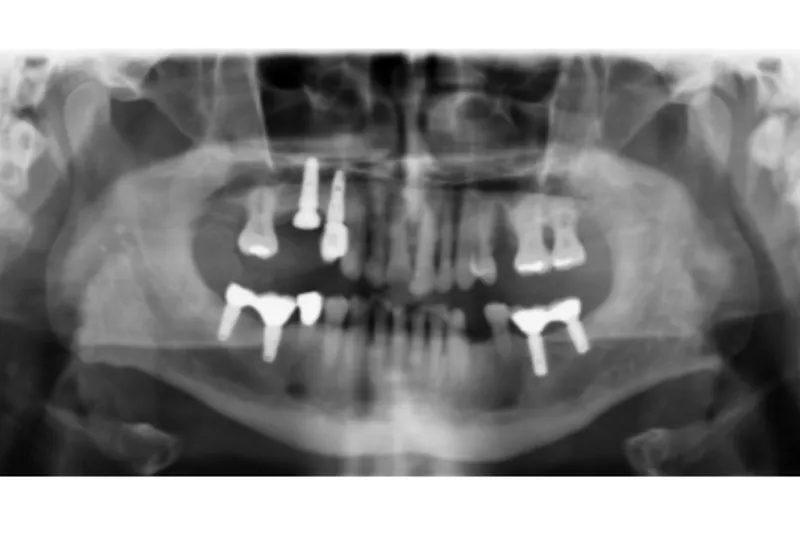

Implantatbehandling har i visse tilfælde overtaget indikationsområdet for både partielle proteser og konventionelle brobehandlinger.

Selvom der er gode kliniske resultater for implantatbehandling, kan der opstå biologiske komplikationer som fx peri-implantitis, tekniske komplikationer som fx chipping af dækporcelæn, mistet retention af suprastrukturen eller, i sjældne tilfælde, fraktur af implantat eller implantatkomponenter.

Selvom komplikationerne kan være alvorlige, er implantatbehandlingen forbundet med høj grad af patienttilfredshed hvad angår både funktion og æstetik.